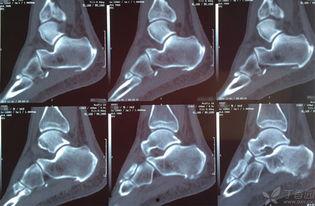

3. 健康指标:颈部骨骼长度也与颈椎健康息息相关。因此,关注双颈91mm骨长70,有助于我们了解自己的颈椎健康状况。

4. 定期检查:定期进行颈椎检查,及时发现并解决颈椎问题。